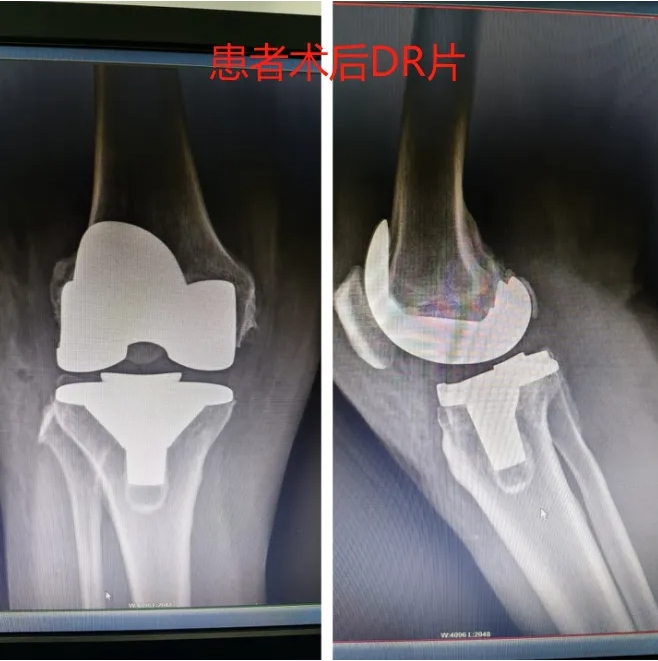

创伤外科团队在接诊后,迅速对患者进行了详细的病史询问和全面的检查。经诊断,刘女士被确诊为膝骨性关节炎。鉴于病情严重,且影响到患者的日常生活,创伤外科专家团队经过研究,为患者精心制定了治疗方案。在与患者充分沟通并取得同意后,手术如期进行。

术后第二天,刘女士便能在医护人员的协助下下床活动,且膝关节的疼痛感得到了明显缓解。为了确保患者能够尽快康复,创伤外科还制定了个性化的康复方案。在医护人员的专业指导和细心照料下,刘女士的恢复情况非常理想。